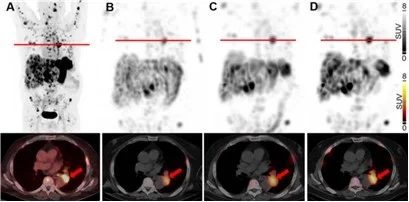

Remarkably, first single patient therapy at University Hospital Basel validated our strategy for enhanced uptake of radiolabeled minigastrin in everolimus-treated MTC patient (Fig. 5) [Rottenburger et al., 2025. J Nucl Med]. Funded by the Swiss National Science Foundation (SNF), we are currently expanding our radiobiology study. This research explores how the location of therapeutic targets - such as internalized or membrane-bound proteins on cancer cells, proteins on surrounding microenvironmental cells (e.g., fibroblast activation protein (FAP) on cancer-associated fibroblasts (CAF)), or extracellular proteins (e.g., fibronectin), and the type of radioactive emitter used (β-, α, or Auger electrons) influence the effectiveness of targeted radiotherapies at the cellular and molecular levels.

Fig. 5.

Maximum-intensity projections and transaxial slices of 68Ga-PP-F11N PET/CT (A) and posttherapeutic, quantitative SPECT/CT 72 h after the 1st (B), 2nd (C) and 3rd (D) RLT cycle of 177Lu-PP-F11N, showing metastatic tracer uptake, increasing with the number of RLT cycles. Two weeks prior the 3rd RLT cycle, the patient received additionally 10 mg everolimus daily, resulting in a further increase of tumor uptake. Red arrows indicate a mediastinal tumor lesion. Adapted from Rottenburger et al., 2025. J Nucl Med.